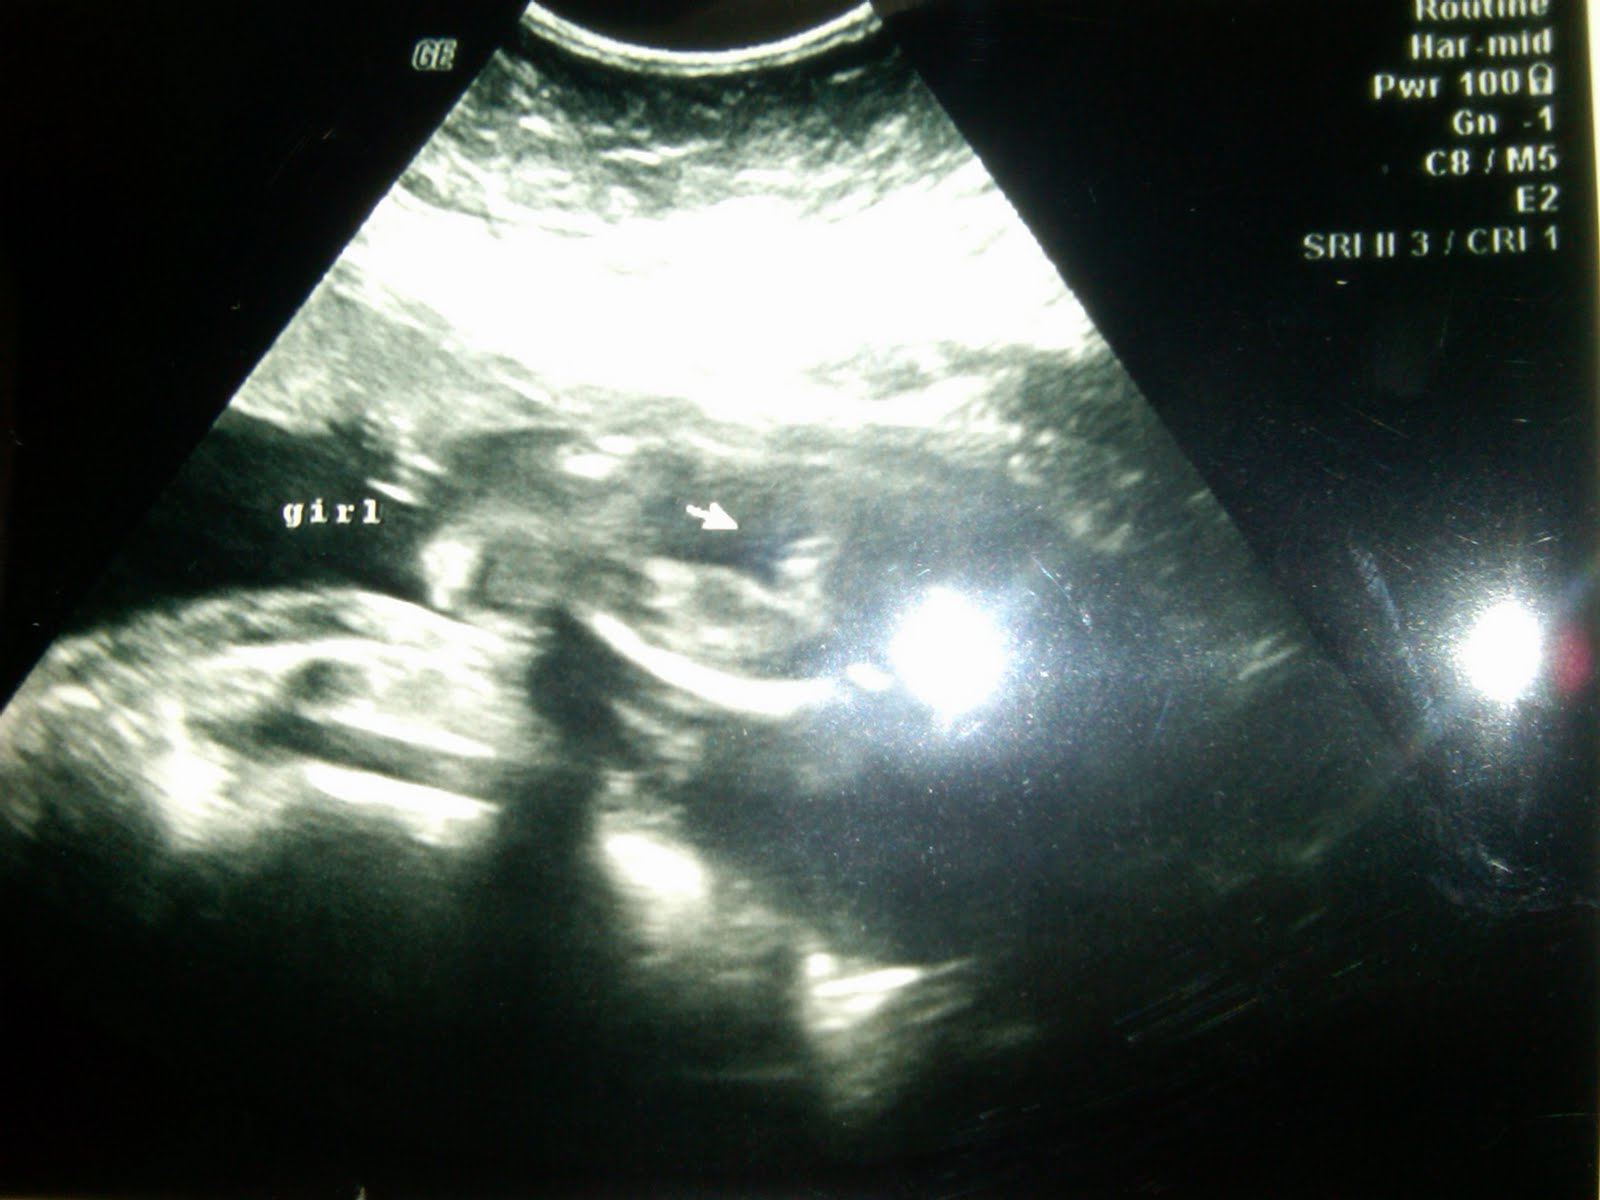

Baby Dyer at 20 weeks-look at that spine!

Another shot at 20 weeks.